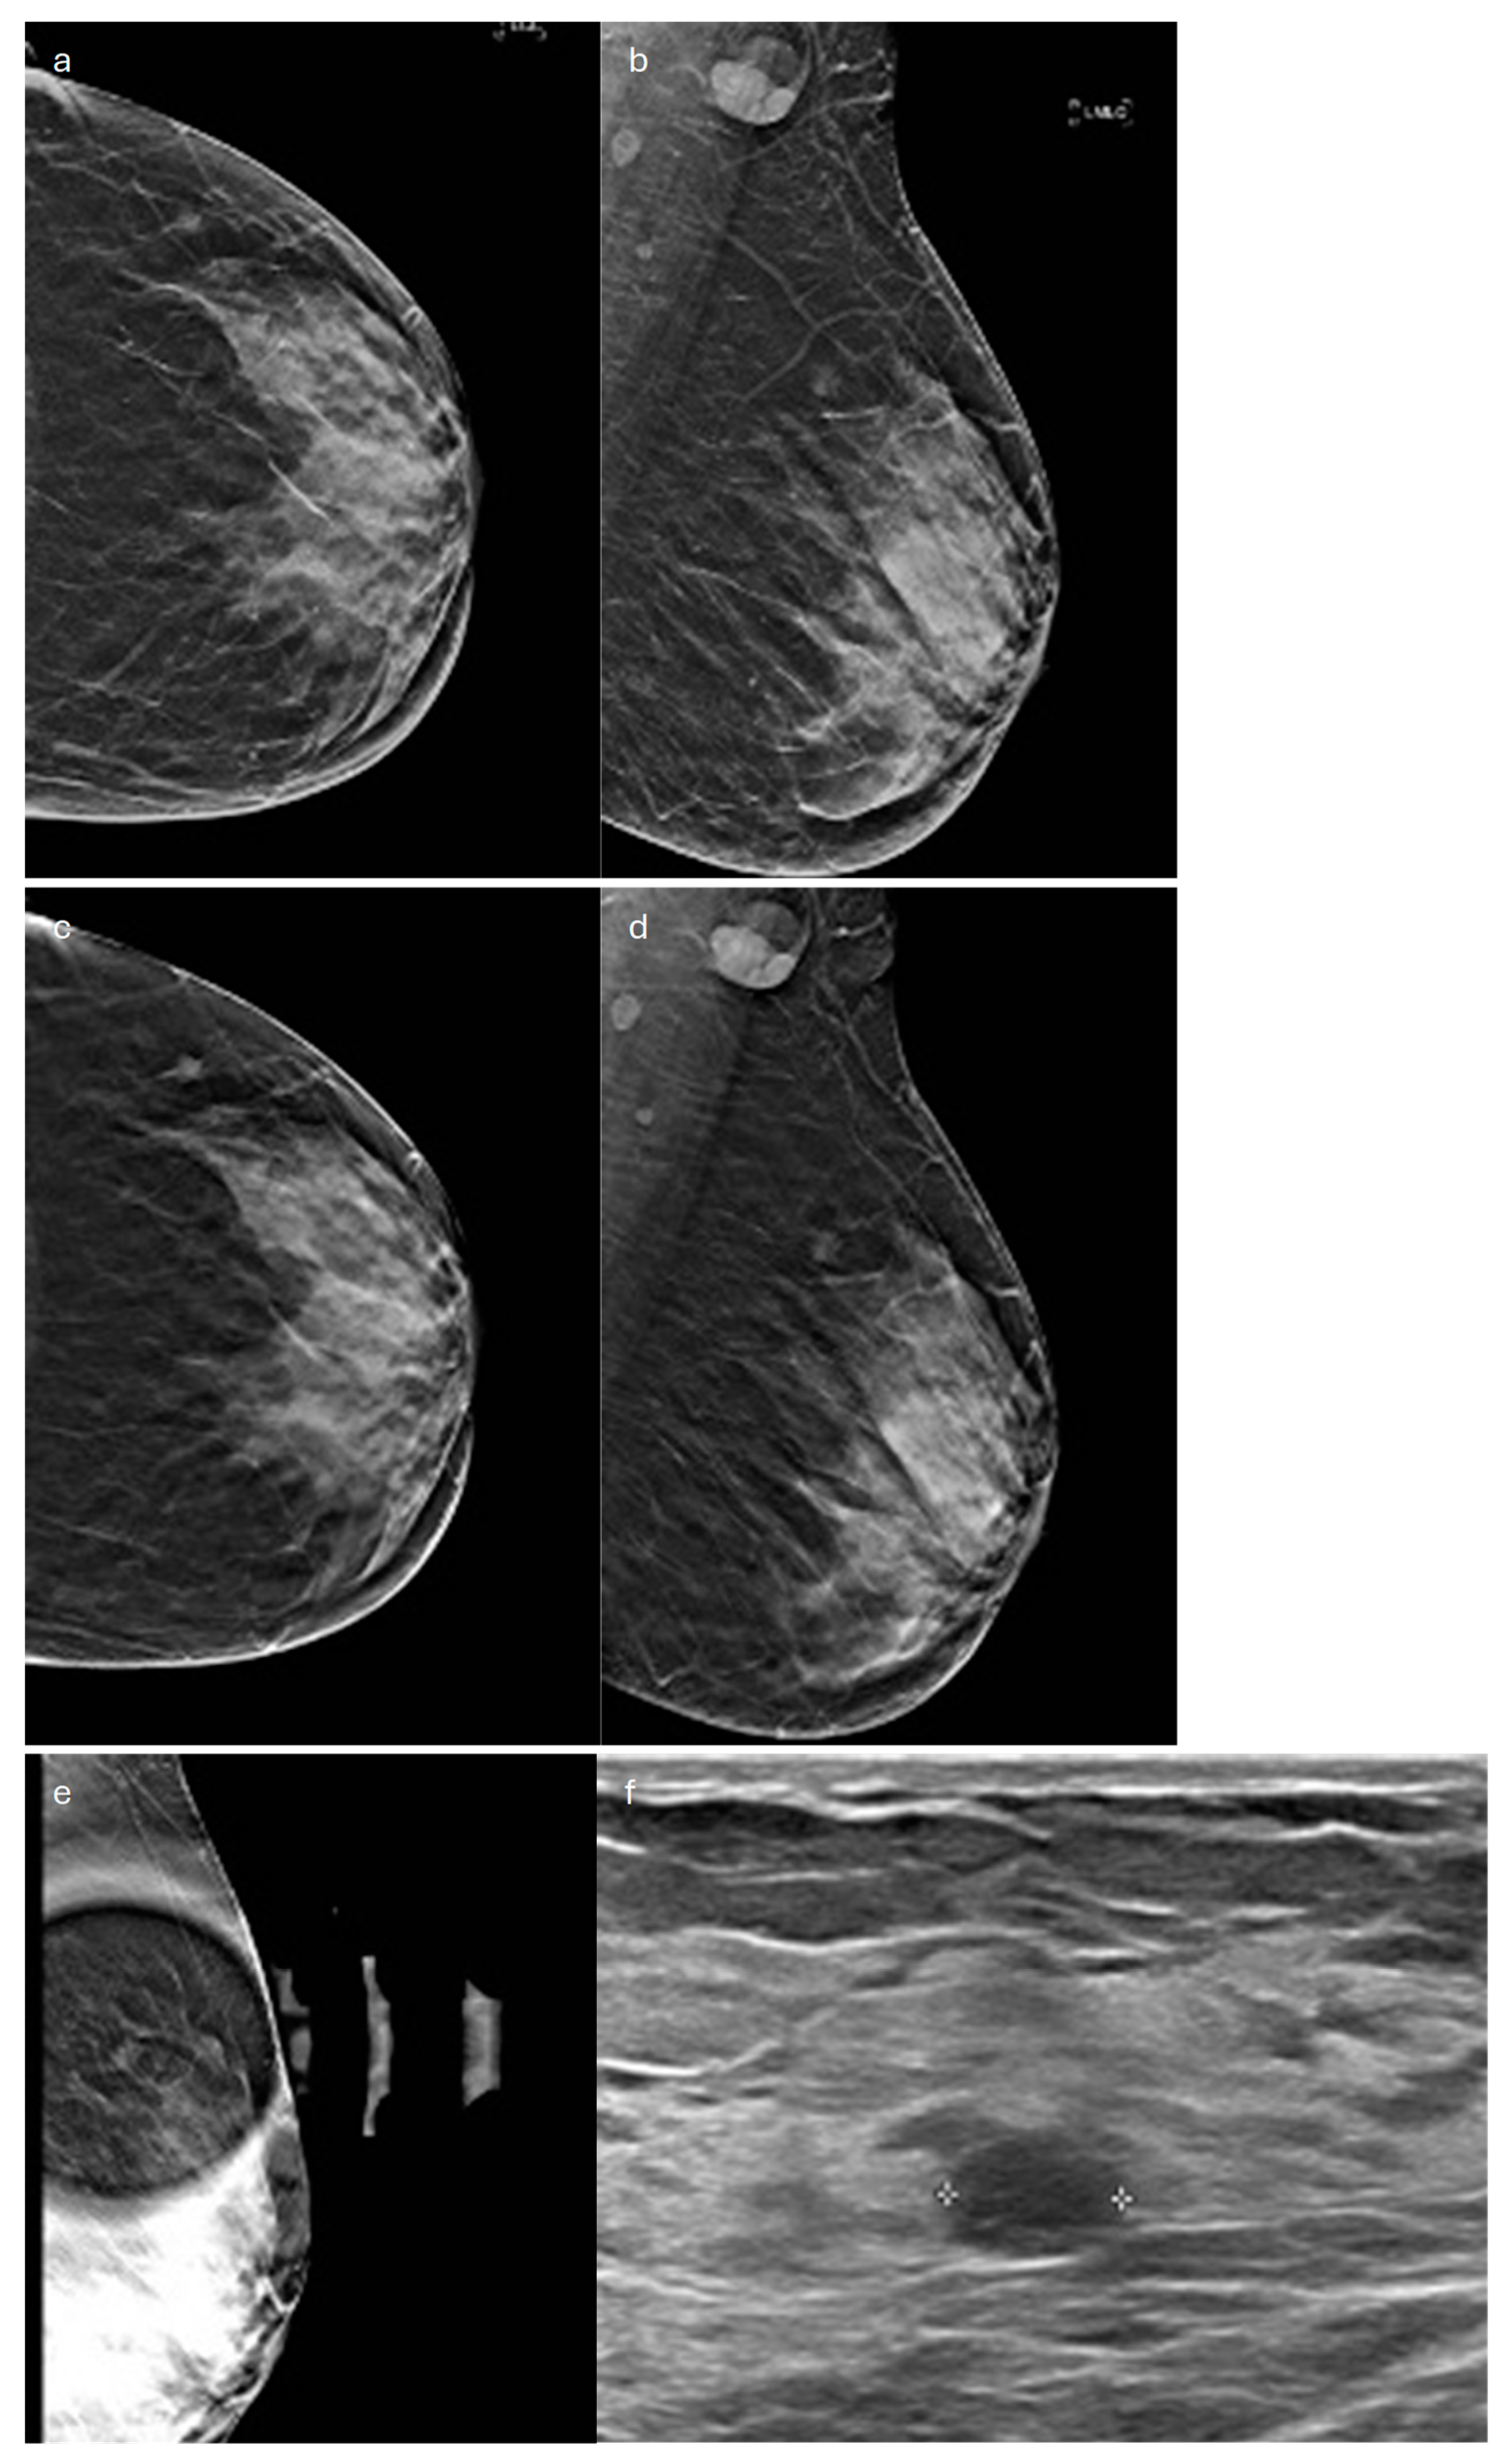

2. Lobular (Classic, Pleomorphic and Florid Types)

- Romanucci, G.; Zantedeschi, L.; Ventriglia, A.; Mercogliano, S.; Bisighin, M.V.; Cugola, L.; Bricolo, P.; Rella, R.; Mandarà, M.; Benassuti, C.; et al. Lobular Breast Cancer Conspicuity on Digital Breast Tomosynthesis Compared to Synthesized 2D Mammography: A Multireader Study. J. Imaging 2021, 7, 185. [Google Scholar] [CrossRef]

- Grubstein, A.; Rapson, Y.; Morgenstern, S.; Gadiel, I.; Haboosheh, A.; Yerushalmi, R.; Cohen, M. Invasive Lobular Carcinoma of the Breast: Appearance on Digital Breast Tomosynthesis. Breast Care 2016, 11, 359–362. [Google Scholar] [CrossRef] [PubMed]

- Dołęga-Kozierowski, B.; Lis, M.; Marszalska-Jacak, H.; Koziej, M.; Celer, M.; Bandyk, M.; Kasprzak, P.; Szynglarewicz, B.; Matkowski, R. Multimodality Imaging in Lobular Breast Cancer: Differences in Mammography, Ultrasound, and MRI in the Assessment of Local Tumor Extent and Correlation with Molecular Characteristics. Front. Oncol. 2022, 12, 855519. [Google Scholar] [CrossRef] [PubMed]